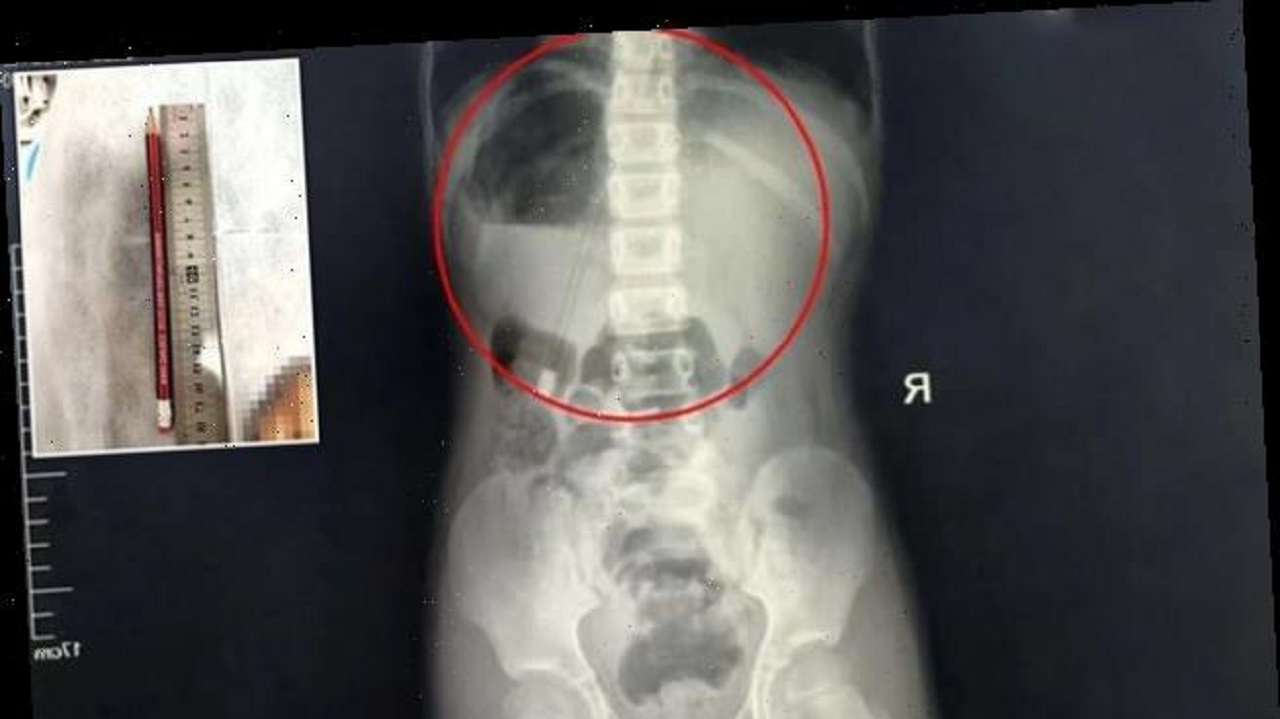

اما اتفاقی که به تازگی برای یک کودک چینی رخ داده است نتیجه تماشای یک برنامه تلویزیونی با محتوای نامناسب را به والدین گوشزد میکند. این کودک که با دیدن صحنهای در یک برنامه سرگرمی تلویزیون که در آن استاد کونگ فو اقدام به فروبردن شمشیر به داخل دهان خود کرده بود یک مداد را بلعید. این کودک ۷ ساله پس از وارد کردن مداد به داخل دهان خود، با فشاردادن سر مداد، آن را وارد معده خود کرد. او در حال انجام تکالیف مدرسه بود که دست به این اقدام زد. پس از این حادثه والدین کودک فرزند خود را سراسیمه به بیمارستانی در استان «هنان» رساندند. آزمایش اسکن این مداد ۱۸ سانتی متری را که وارد معده کودک شده بود به خوبی نشان میداد.

این کودک بلافاصله تحت عمل جراحی قرار گرفت و جراحان موفق به خارج کردن مداد از بدن کودک شدند. یکی از جراحان در این باهر به رسانههای محلی چین گفت: «این کودک بسیار خوش شانس بود، چون سر مداد در بالا قرار گرفته بود و انتهای مداد وارد معده او شده بود. این درازترین شی خارجیای بود که من در طول ۱۰ سال جراحی ام از بدن یک بیمار خارج کرده ام.»